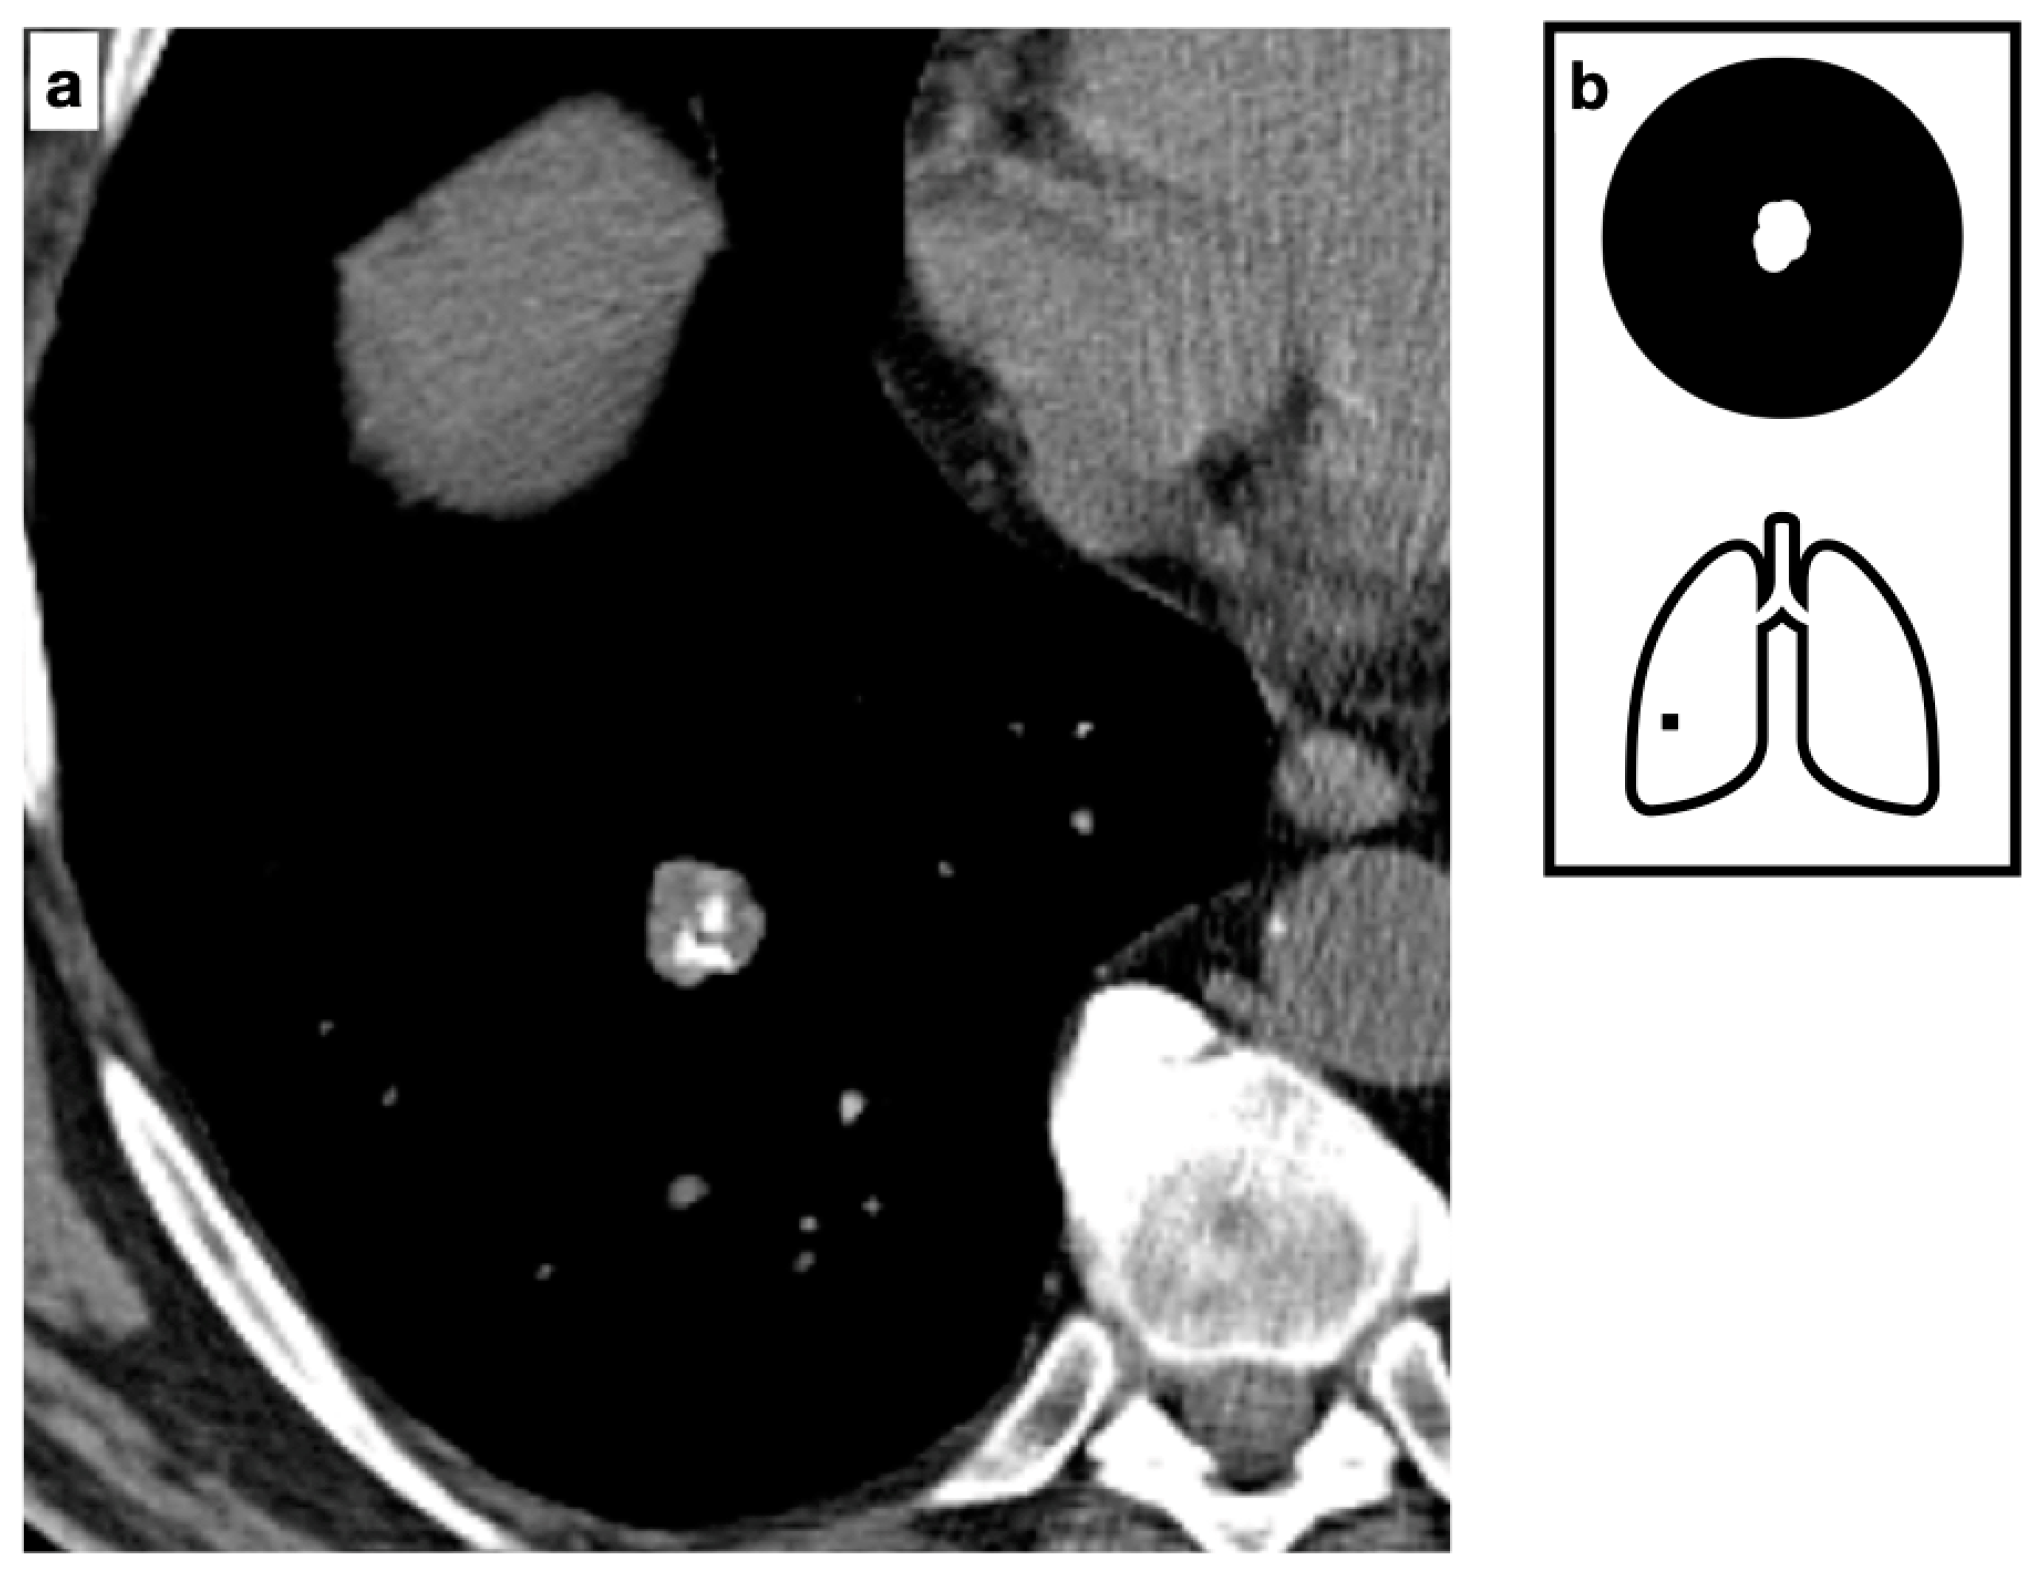

Figure 9.

CT axial images demonstrate a peripheric lung nodule characterized by spiculated margins, small cavitation and an eccentric calcification; this lesion was a biopsy-proven adenocarcinoma (a,b). Heavy smoker patient with severe confluent centrilobular emphysema. HRCT shows a malignant nodule with a small eccentric calcification in the right upper lobe (c). A spiculated nodule with a relatively fast growth rate must always raise the concern for lung cancer in patients with smoking history. Pattern of calcification (d).